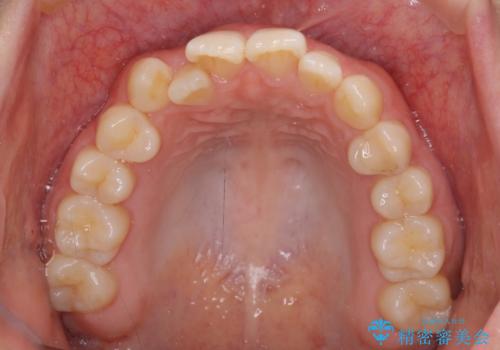

- 前歯のクロスバイトを気にして来院された患者様です。

治療前にお伝えした治療期間は1~1年半でして、1年4か月の期間で終えることができました。